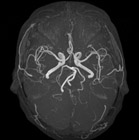

(脳血管)